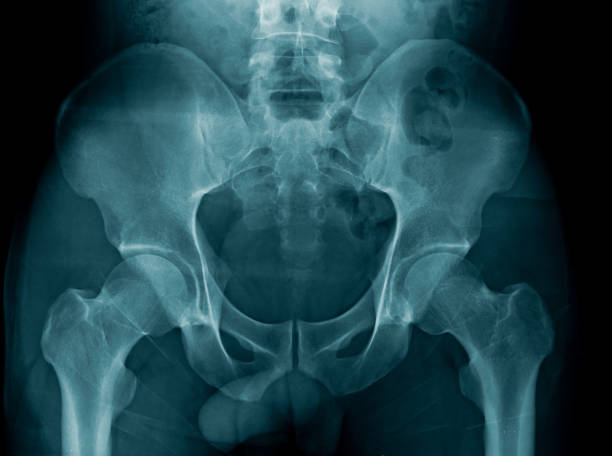

척추관협착증은 척추 주변의 근육과 인대가 퇴행하여 척추관 내 황색 인대가 비정상적으로 부풀어 오르면서 발생하는 퇴행성 척추질환 중 하나입니다. 이 질환은 가까운 거리도 통증으로 인해 걷기가 어려워지는 특징을 가지고 있으며, 새벽에 다리에 통증을 느끼는 경우가 많습니다.

척추관협착증은 다른 척추 질환에 비해 퇴계 정도가 매우 심한 질환으로, 퇴행이 심할수록 근육과 인대가 더욱 뭉쳐지고 더 많은 압력을 가하게 됩니다. 이 때문에 근육과 인대를 풀어주는 것이 중요하며, 이를 위한 가장 적합한 운동이 걷기입니다.